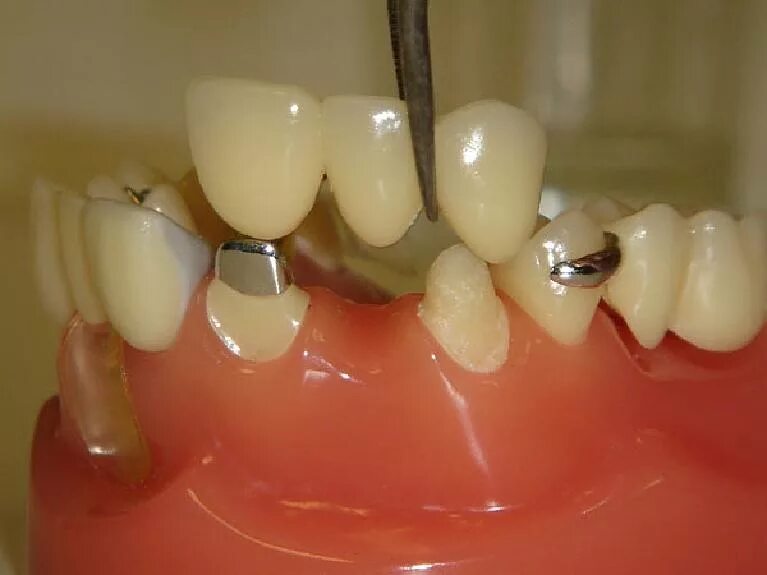

Поставить 4 зуба